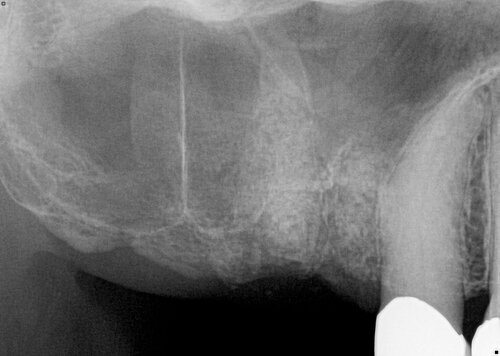

Pre-treatment dental images for patient evaluation

Before

This patient was congenitally missing these front teeth, which never developed.